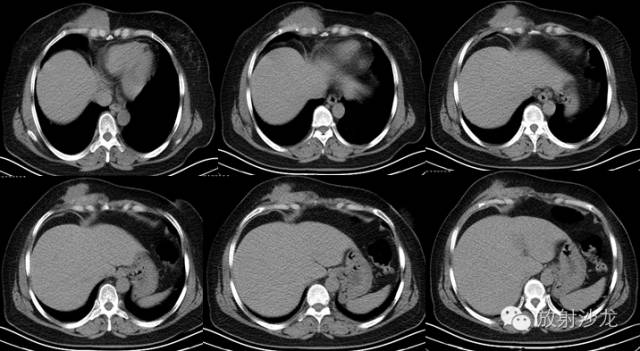

2. 主 诉:发现右侧前胸壁肿物伴间断疼痛3年,进行性增大1年

3.现病史:约3年前发现右侧前胸壁肿物,初始发现时约1cm×1cm大小,伴钝性疼痛,呈间断性,休息后缓解,不伴胸憋、气紧、咳嗽、发热、盗汗等症状,不伴牵扯性疼痛,未予重视。1年前右侧前胸壁肿物进行性增大,仍伴间断性疼痛

4. 专科检查:胸廓无畸形,双乳对称,无红肿,无触痛。右侧前胸壁可触及一大小约13cm×6cm的不规则形皮下肿物,越过胸骨正中线,表面不平,其上可见两处范围分别为4cm×3cm、2cm×1cm的皮肤发红区域,触之质韧,边界不清,活动度差,无皮温增高及波动感,无明显压痛

CT表现:CT对侵袭性纤维瘤病的诊断无特异性,CT常表现为肿瘤沿肌肉长轴生长,边缘规则或不规则,密度基本均匀,增强扫描可见强化。CT扫描能提示病变的性质并能正确评价病变侵犯的范围,对制订恰当的治疗方案及减少复发机会有明显价值口。